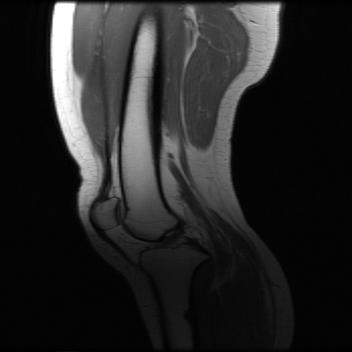

Test data: For evaluation, we used the ten 352352 MRI images in Fig. 2, which were not in the training dataset. The measurements were constructed using (1) with complex AWGN whose variance was adjusted to give a pre-masking SNR of 40 dB. For the multicoil experiments, we used coil sensitivities simulated using the Biot-Savart law, while in the single-coil case, we used .

Single-coil results: Table 1 shows that D-GEC outperformed D-VDAMP in all single-coil experiments and outperformed PnP-PDS in all but SSIM at . Figure 5 shows an example of the wavelet coefficients input to D-GEC’s denoiser at the 10th iteration, and their error relative to the true coefficients. Figure 3 shows the evolution of the standard deviation at the input to D-GEC’s denoiser in each subband; there is a good agreement between true and predicted values. Figure 6 suggests that the subband errors are Gaussian. Figure 4 shows image recoveries and error maps for one test image at .